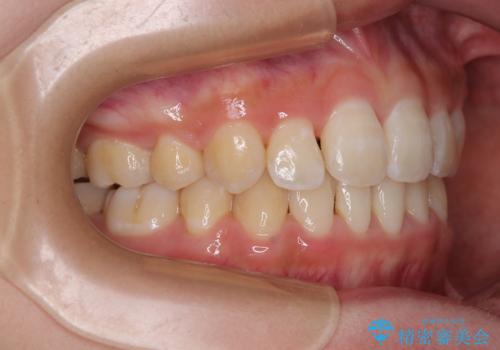

- 前歯のデコボコと唇の閉じにくさを気にして来院された患者様です。

単純に上下左右の第一小臼歯4本を抜歯して口元の突出感を改善することも考えられましたが、上顎骨よりも下顎骨の幅が広いため、より良い咬み合わせを達成することを目的として、急速拡大装置を用いて上顎骨を拡大することとしました。